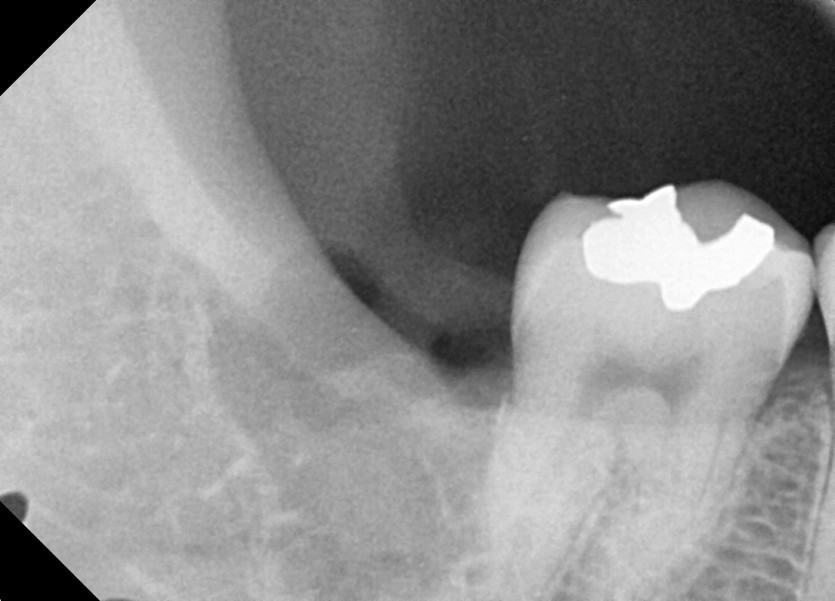

#48 사랑니 발치

구강 외과 전문의가 당일 발치했습니다.